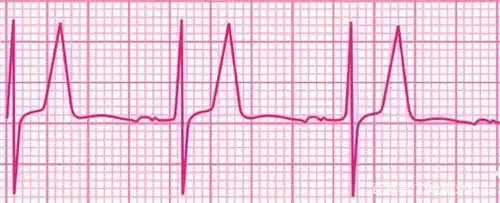

大家看看这高尖的t波是什么诊断

高钾血症的高尖t波,如"埃菲尔铁塔"

心电图st段下斜型压低合并t波高尖的急性心肌梗死一例